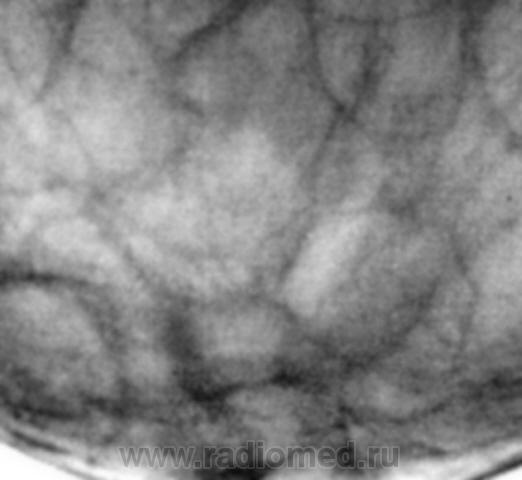

"Уплотнение" пропальпировано хирургом в передних отделах молочной железы...

На представленных снимках патологии нет, но учитывая наличие пальпируемого уплотнения нельзя исключить липому.

а практически по центру на всех маммограммах: разве не мелкий узел с тяжистым контуром, примерным размером 1.5-2 см (масштаб не ясен). такие вещи в ГО: аденокарцинома